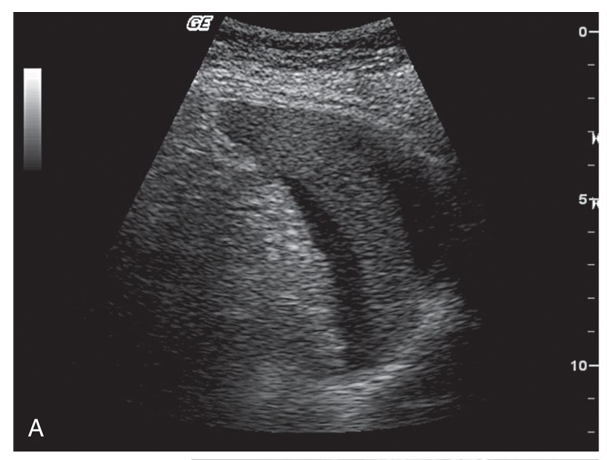

Splenic hematoma: Separation of the splenic capsule from the spleen secondary to a large hematoma resulting from an automobile accident.